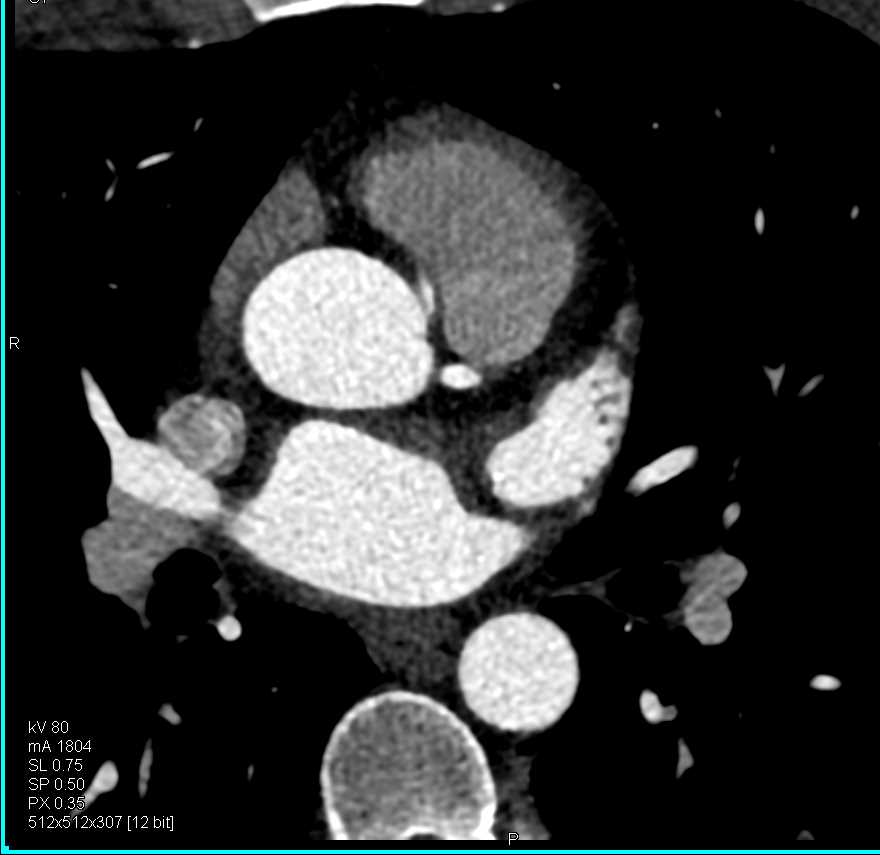

RCA Arises off Left Coronary Artery in Malignant Configuration